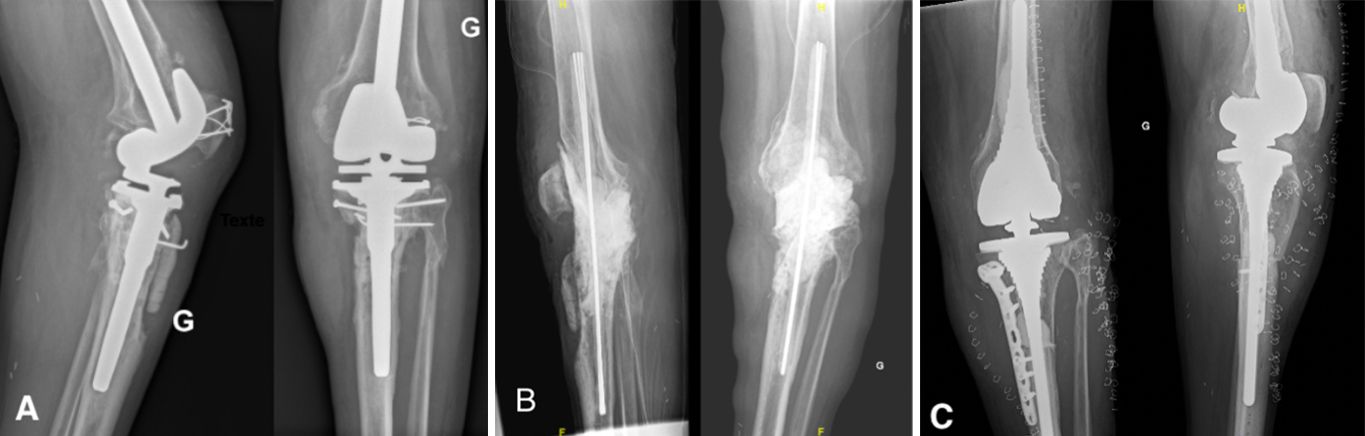

Step 3: Making the static spacer

The firsts step is the fashioning of a rigid rod of cement reinforced by Kirschner wires to reduce the very high risk of spacer fracture. 3-4 wires of 2 mm diameter should be used and coated with high-viscosity antibiotic cement. When the mixture starts to solidify, it is molded manually by the surgeon (Fig.2).

The length must be long enough to have at least 6 cm of rod in each femoral and tibial canal, plus the length of the joint space to bypass the joint and be stable and strong enough. Once set, this rod, marked at its center, is introduced back and forth into the femoral and tibial canals until the center mark is at the midpoint of the joint space (Fig.3). We usually use 1 cement package of 40 g for this rod.

Next, the whole spacer is prepared using high-viscosity antibiotic cement. We use cement with Gentamycin and add crystalline Vancomycin, 1g per cement package. The Vancomycin should be added to the cement before being added to the liquid monomer [13]. If the Vancomycin is added later, the mixing is inconsistent due to poor dissolution and risks unequal diffusion into the soft tissues. We advise adding methylene blue to the preparation. We usually use 1 mL, added just at the start of mixing, to obtain a homogenous blue paste (Fig.4). The methylene blue is added to the cement to provide easy discrimination between native bone and cement and facilitate cement removal during the second stage of surgery [25].

The spacer should fill the joint space to maintain the native leg length. 2 minutes after the second cement mixture, the joint is opened with traction on the leg in extension to fill any bone defects and the joint space with cement. The size of the spacer should be appropriate but not too large to avoid excessive skin tension during wound closure. This second cementation stabilizes the construct and prevents spacer migration (Fig.5). The joint capsule, subcutaneous tissues, and the skin are closed in layers.

During the second stage of surgery, the surgeon removes the cement by breaking the spacer and removing the rod spacer. It is easier to cut the wires and remove the rod in 2 parts. Another thorough debridement is performed and samples are taken before implantation of the new definitive prosthesis.